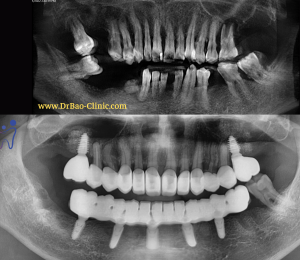

- Kèm theo tình trạng mất răng sau hàm dưới

- Trồng răng implant phục hồi răng mất phía sau

Kết quả sau khi trồng răng implant phía sau hàm dưới

Sau khi hoàn tất răng trên implant, chúng tôi bắt đầu bước sang giai đoạn thẩm mỹ răng phía trước hàm trên.